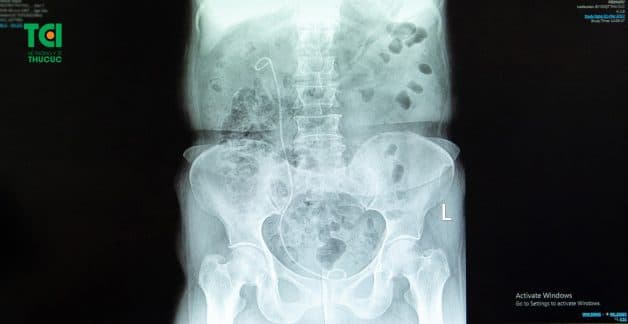

Bệnh nhân được đặt sonde JJ sau tán sỏi thận tại TCI